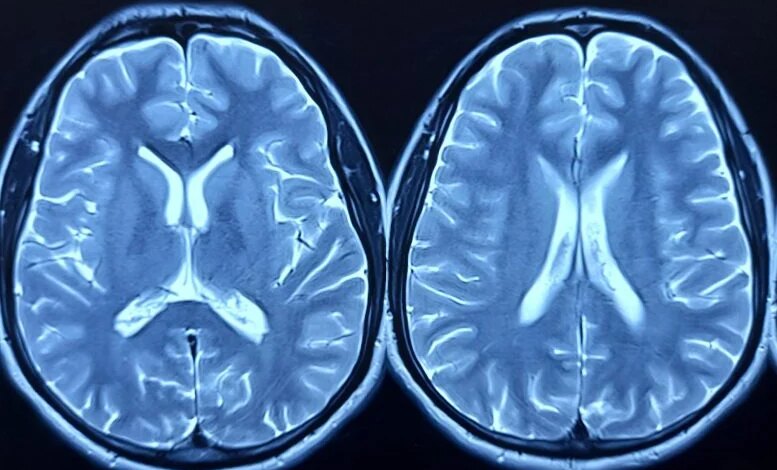

أكبر دراسة لأنسجة المخ الأمريكية الأفريقية تكشف عن الجين الخطير لمرض الزهايمر

يظهر التوقيع الجزيئي المشترك لمرض الزهايمر بين المجموعات السكانية التي تمت دراستها بمعزل عن غيرها. يؤثر مرض الزهايمر (AD) على الأمريكيين من أصل أفريقي (AA) بمعدل ضعفي المعدل تقريبًا بين الأفراد ذوي الأصول البيضاء / الأوروبية (EA) في الولايات المتحدة. ويرتبط هذا التفاوت جزئيا بالمحددات الاجتماعية للصحة، بما في ذلك عدم المساواة في الحصول على الرعاية الصحية، والاختلافات في جودة التعليم، والتحيزات (…)